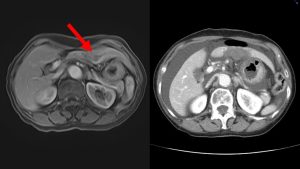

乳癌肝転移(3病変)と大腸癌肝転移を治療しましたが、2例ともスムーズに治療を終えることができました。翌朝のCT検査で、すべての病変の完全な焼灼が確認されました。合併症や術後の痛みもありませんでした。

Emprintは安定した焼灼範囲が得られますが、150Wモデルトは100Wモデルと比較してもより短時間で、より大きな焼灼域が得られます。